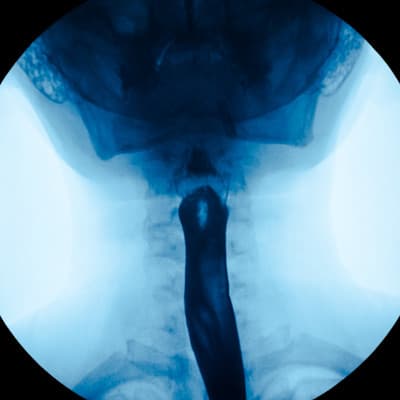

The colon — also known as the large intestine — is where stool is formed, stored, and then pushed out.

A colonoscopy is a test uses a small tube with a mounted camera and light on it to look directly at the lining of the colon. Your child may need a colonoscopy if they have blood in their stool, diarrhea, or abdominal pain.